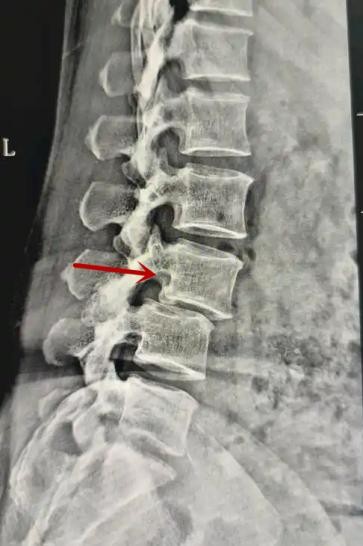

箭頭提示腰1椎骨折

箭頭提示腰3椎體滑脫